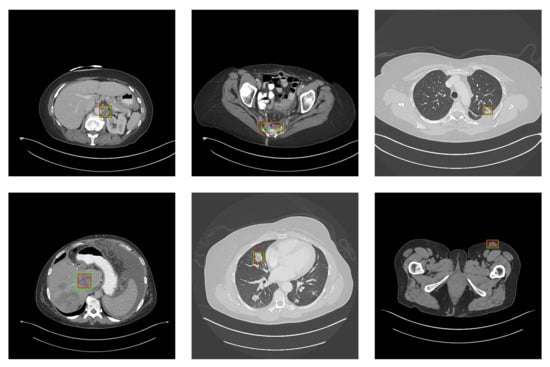

5.2. Detection Results

For further comparison, we extracted six images from the CT image series of DeepLesion. These images were taken from different sites of lesions and different areas of lesions, showing the detection results of the comparison model as comprehensively as possible. Figure 10, Figure 11, Figure 12, Figure 13, Figure 14, Figure 15, Figure 16, Figure 17, Figure 18 and Figure 19 show the detection results. All green boxes represent ground truth; red boxes denote predicted bounding boxes. It can be seen that Faster-RCNN performs very poorly on small lesions and lesions that are not easy to identify, while YOLO v3, YOLO v4, and SSD series perform relatively well. However, the aspect regression of the bounding box at small lesion locations is still not accurate. On the other hand, EfficientDet, Mask-RCNN, and YOLO v5 perform relatively well and detect lesions accurately. This may be related to the attention extraction module in these networks.

Figure 10.

The detection results of YOLO v3 in the DeepLesion dataset. The green box marks the location of the lesion.